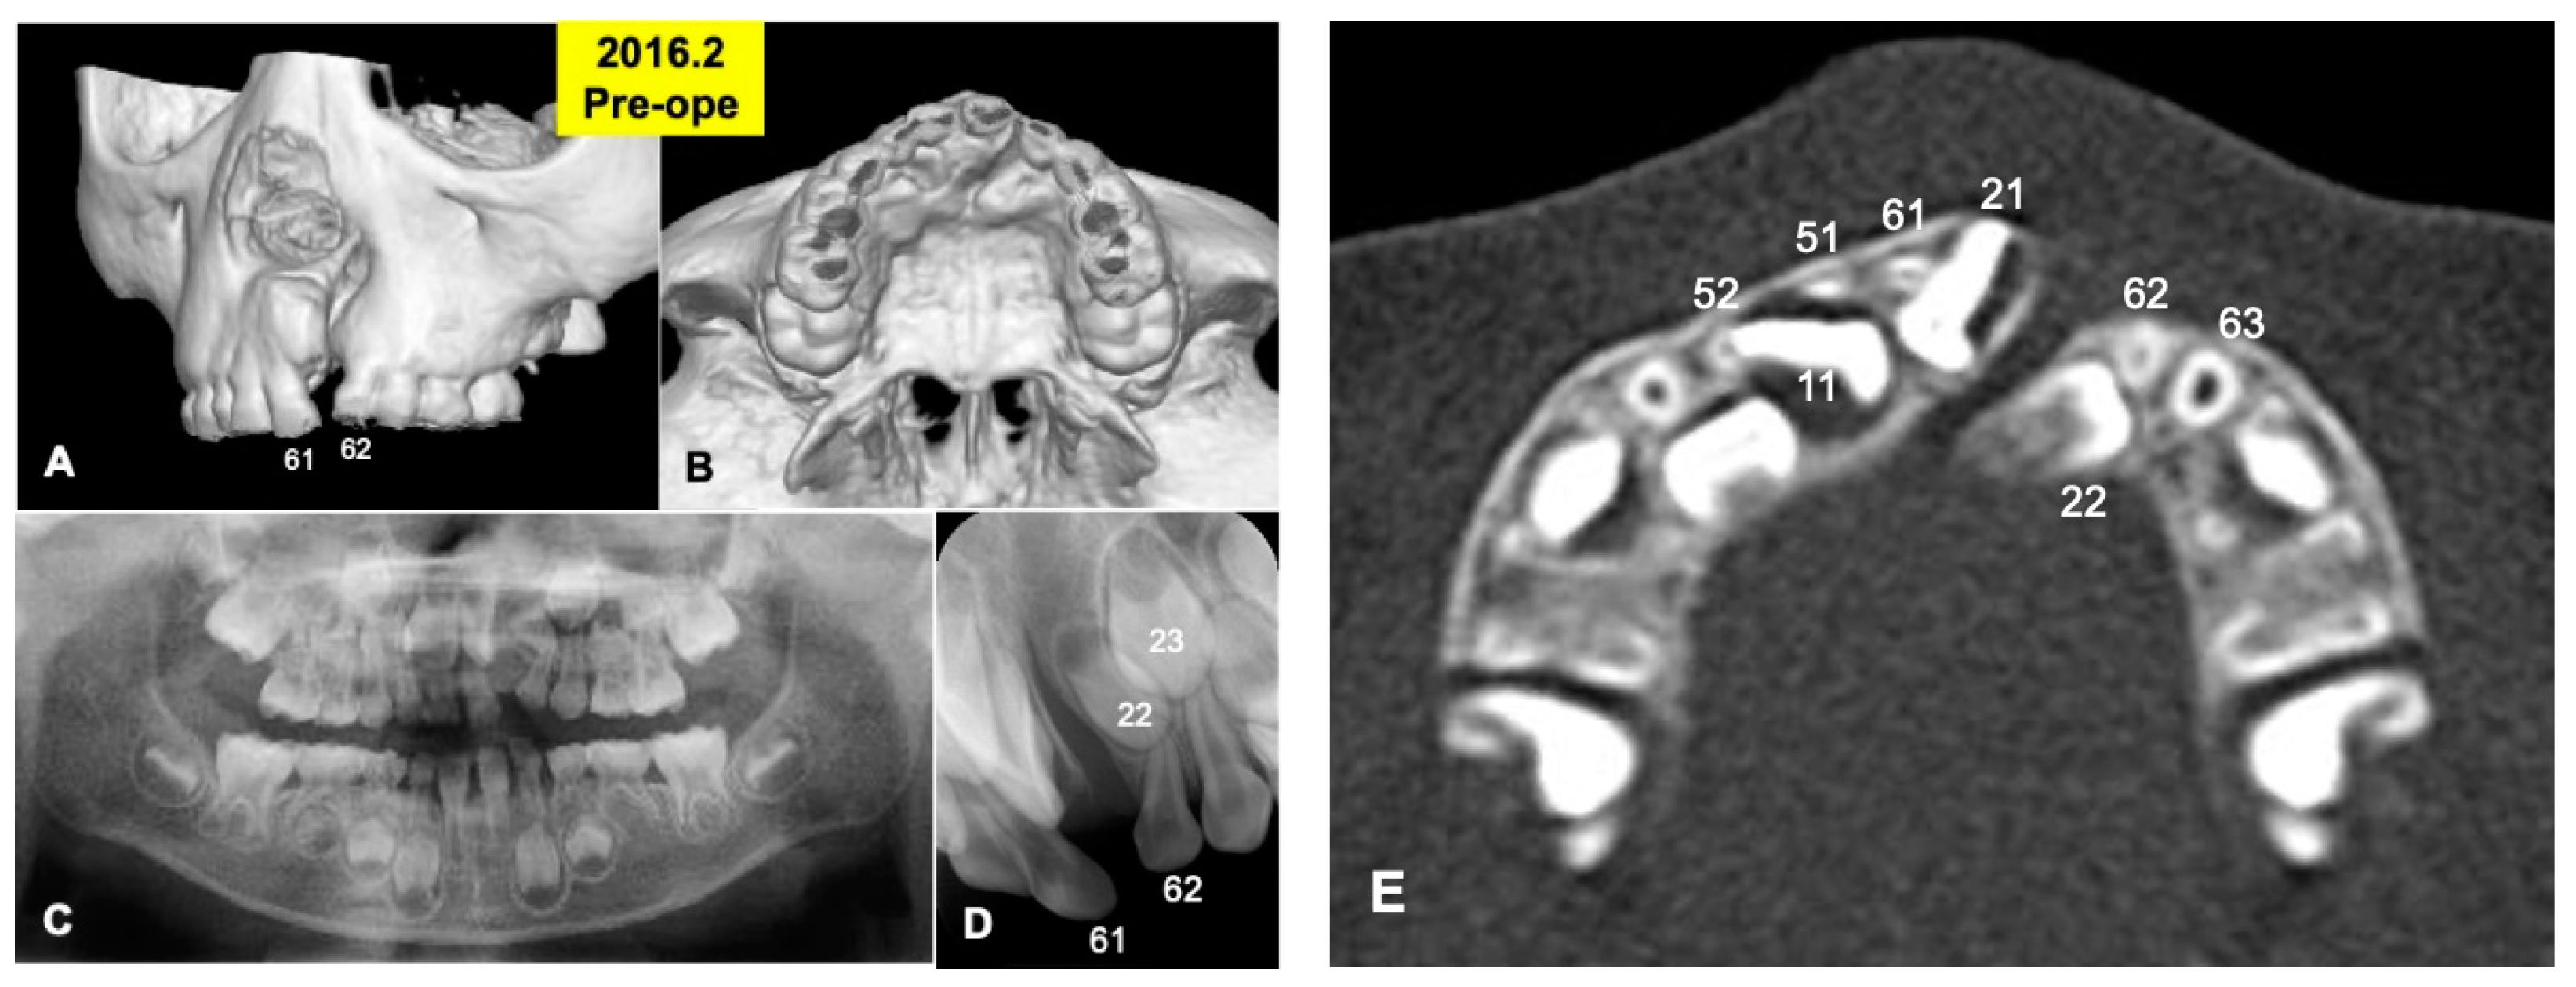

Gross View and Radiographic Evaluation after Surgery